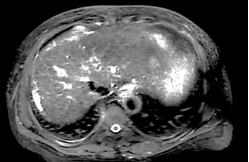

Ø 术前影像学检查

肝 S2 段及肝 S4 段见类圆形 T1WI 低、T2WI-SPAIR/DWI/ADC 高信号,较大者长径

约 10mm,界清。

T2 SPIR 横轴位